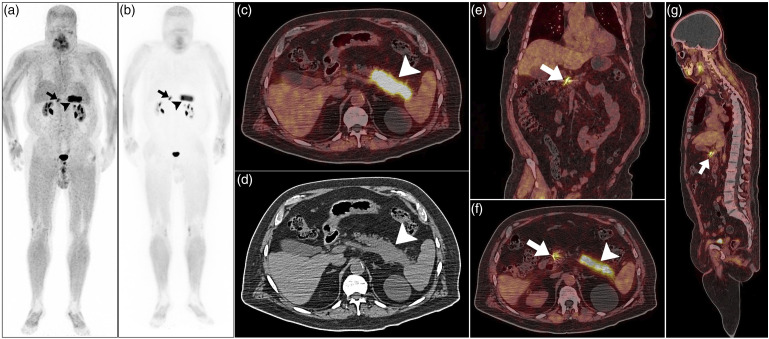

Intense fibroblast activation protein inhibitor localization around the site of embolized gastroduodenal artery in a patient with metachronous pancreatic adenocarcinoma: A potential pitfall in positron imaging.

68Gallium-Fibroblast activation protein inhibitor (68Ga-FAPI) positron emission tomography/computed tomography (PET/CT) is increasingly used for evaluating various epithelial neoplasms. Despite addressing some pitfalls, many remain unacknowledged. This report details a 77-year-old man with suspected pancreatic malignancy who underwent a 68Ga-FAPI PET/CT scan post-gastroduodenal coil embolization for upper gastrointestinal bleeding. The scan revealed intense 68Ga-FAPI uptake in the pancreatic body and tail malignancy and around the embolized gastroduodenal artery, indicating a healing process. This highlights the importance of understanding FAPI expression in recent surgical sites for accurate radiologic interpretation.